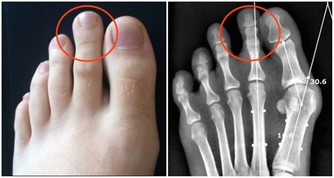

肺對人體的最大貢獻就是供氧氣、排廢氣。這個器官出問題,人體會不能得到足夠的氧,或者累積過多的廢氣廢物。一方面,氧是組織細胞賴以生存和發揮作用的基礎物質,沒有它,臟器罷工,人就不能正常生存。另一方面,廢氣堆積,會進一步損害肺等臟器。護肺養肺非常重要。

要看肺好不好,可以憑藉“氣”順不順來判斷一二。

肺好的人有3個特點

*****1.呼吸強有力*****

肺好的人,呼氣吸氣更順暢,特點是呼吸緩慢而且深沉,一口氣能吸入和過濾的氧氣更多,供氧多神清目明。

相反,肺不好的人,呼吸不順暢、呼吸急切,氣淺而短促。

要觀察自己的呼吸質量怎麼樣,可以選在早晨起床後,注意關註一下自己的呼吸的次數和深淺程度。如果有呼吸困難、急促以及胸悶等現象的話,要引起重視。

****2.肺活量大*****

指的是一次盡力吸氣後,再呼出的氣體總量。肺活量是衡量肺部功能的通氣量好壞指標,肺活量越大,人的呼吸比較深入,可以更好地實現氣體交換。

一個成年人的肺活量大約是3000-4000ml,運動員的肺活量可達6000ml,肺活量隨著年齡的增長逐漸變小。

*****3.皮膚潤澤*****

肺功好的人,氧氣入體更多,能隨著全身血液系統更好的供給人體,也包括皮膚的組織細胞。皮膚細胞受到更好的滋養,皮膚的狀態也會更好。反之,肺不好的人,皮膚也會受到印象。

要保護肺,有一點很重要,那就是戒菸,以及多呼吸質量好的空氣。保障充足的睡眠也有助於人體對肺的修復。除此之外,飲食對養肺護肺也很重要!